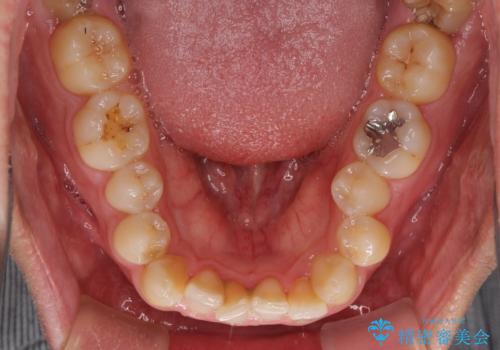

前歯のデコボコとクロスバイト インビザライン矯正治療

- 前歯のデコボコとクロスバイトを治したいとのことで来院された患者様です。

上下顎ともに歯列全体の側方拡大を行い、下顎前歯はIPR(歯と歯の間を削る)によってデコボコとクロスバイトが解消するように設計し、インビザラインにより治療を行うこととしました。

2年弱で終了する予定でしたが、途中来院されなかった時期があり、その後舌側転位している前歯を動かせるところまで動かしたいとのことで4年ほど治療を継続されました。